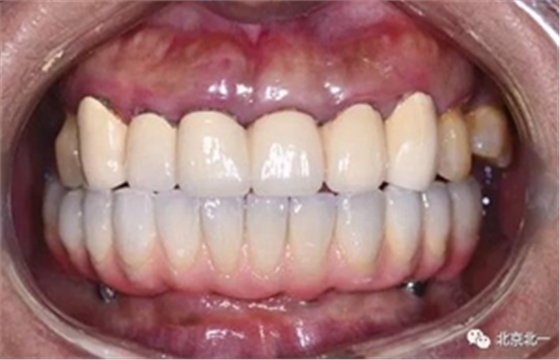

圖十九:永久修復(fù)完成

圖二十:永久修復(fù)咬合關(guān)系